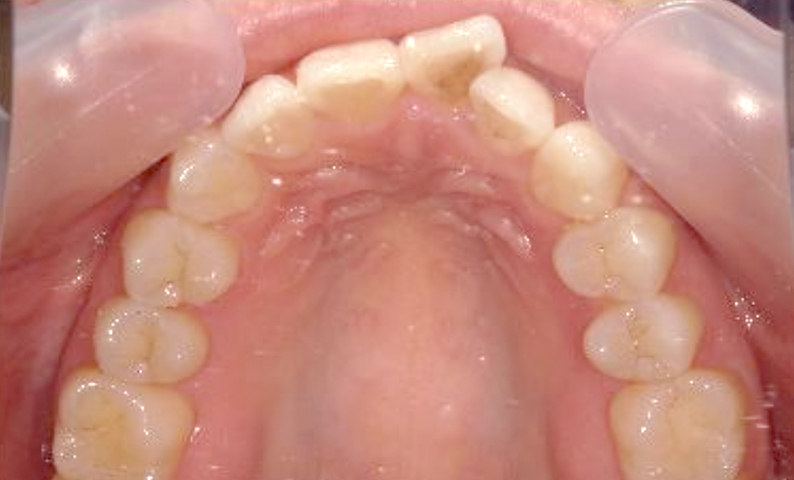

症例:上下顎の部分矯正

症例_002 前歯「捻転歯」症例

治療期間:10ヶ月金額:54万円+税30代女性少しのねじれ捻転歯前歯の突出感